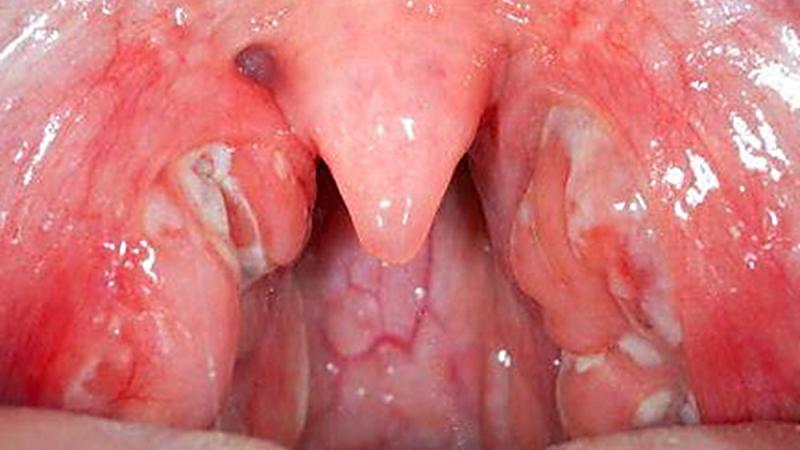

При воспалении небных миндалин пациент испытывает множество неприятных симптомов. К основным из них можно отнести:

- болезненные ощущения при глотании пищи и жидкости;

- покраснение слизистой оболочки;

- изменение цвета миндалин;

- ощущение першения;

- боль в горле;

- налет на миндалинах;

- гнойные выделения;

- белые комочки;

Однако ключевым признаком хронического тонзиллита является отечность небных миндалин и выраженное воспаление в горле. Отек может быть настолько значительным, что приведет к затруднению дыхания.